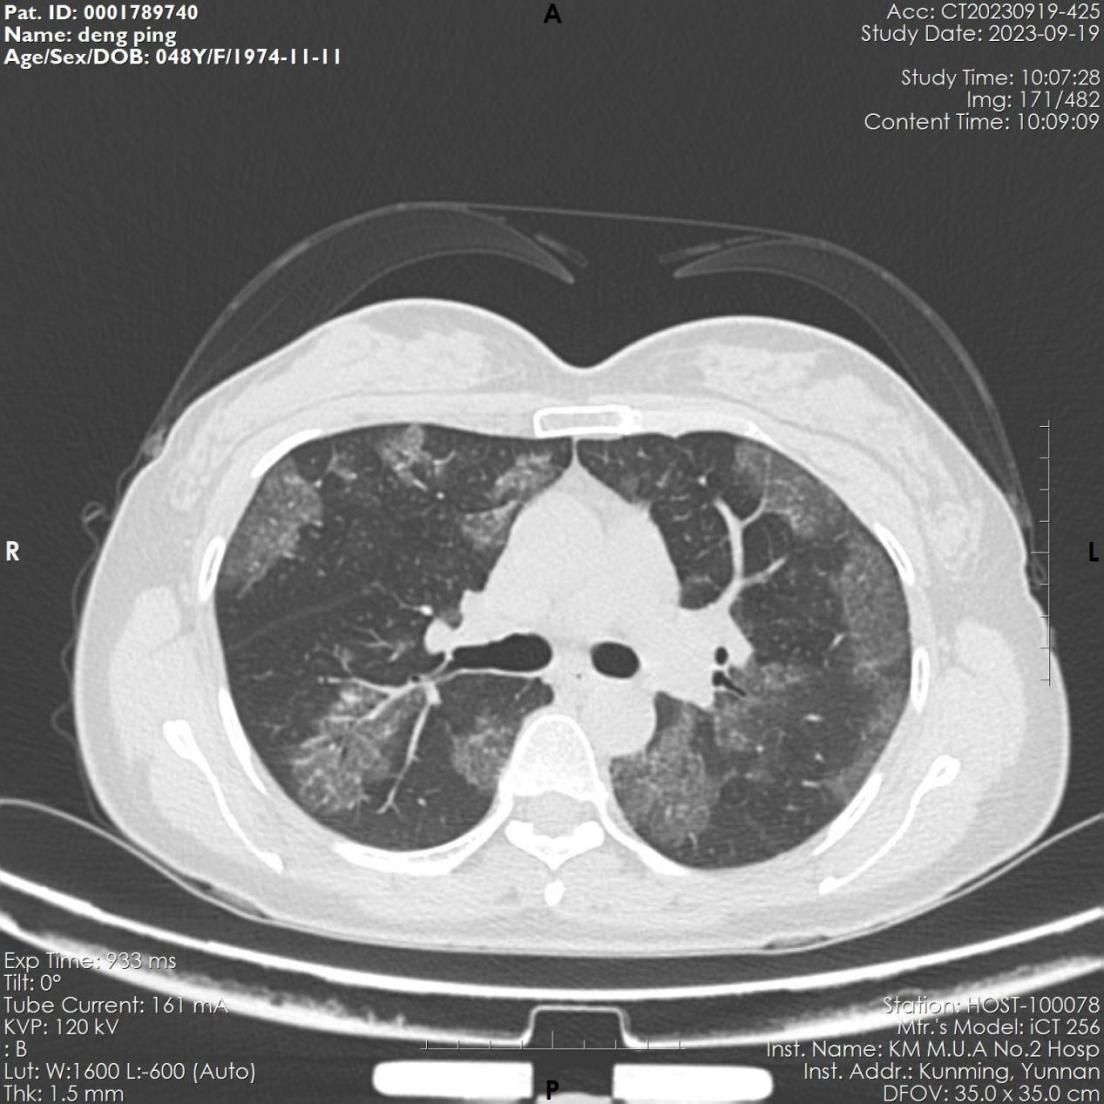

该患者,女,48岁,近3月来反复出现活动后胸闷气促。6月份因感染肺炎住院治疗,经抗病毒治疗后,咳嗽、咽痛等呼吸道症状缓解。9月因胸闷气促再发加重,来到昆医大附二院全科医学科就诊,复查胸部CT显示肺部病变未见吸收,病变呈弥漫磨玻璃影,病变与正常组织分界较清,呈“地图征”,考虑“间质性肺疾病-肺泡蛋白沉积症可能”收住全科医学科。入院后完善电子支气管镜检查示双侧支气管未见明显异常,但各管腔内的肺泡灌洗液呈乳白色,肺泡灌洗液细胞学病理检查示肺泡巨噬细胞中间粉红色颗粒样物质,D-PAS和PAS染色阳性。结合病史、胸部CT、肺泡灌洗液呈乳白色、PAS染色阳性,该患者确诊罕见病“肺泡蛋白沉积症”。